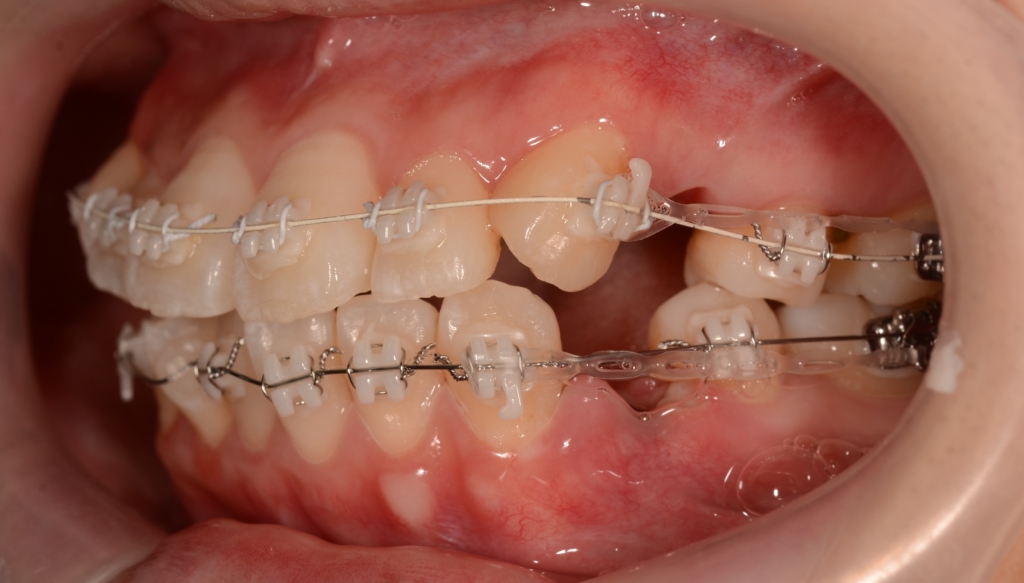

その後、更なる点数アップを目指して仕上げの微調整を続けました。

左側に出っ歯の噛み合わせが残っていたので、左側のみ顎間ゴムを半年間頑張ってもらいました。

また、途中、妊娠&出産が重なり体調を崩したこともあり、約1年弱にわたり通院が出来なくなるなどいろいろありましたが、何とかゴールに滑り込みました。

【After】

矯正治療の結果、狙い通りに口元をスッキリさせることが出来ました。

お口を閉じるのにも「力」が要らなくなり、楽に閉じれるようになった!と喜んでもらいました。

また、Eラインに収めることは出来ませんでしたが、患者さん的には引っ込み過ぎるは嫌なので、元々あった口元の突出感も無くなり、このくらいがちょうど良い!とのこと。

ついでに、歯並びの比較です

上段が矯正治療前、下段が矯正治療後